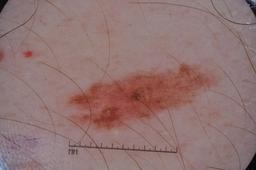

MSK-4

- Name: MSK-4

Description:

Images found based on a search for patients with a personal history, clinical diagnosis, or differential diagnosis of melanoma. All diagnoses confirmed by histopathology.